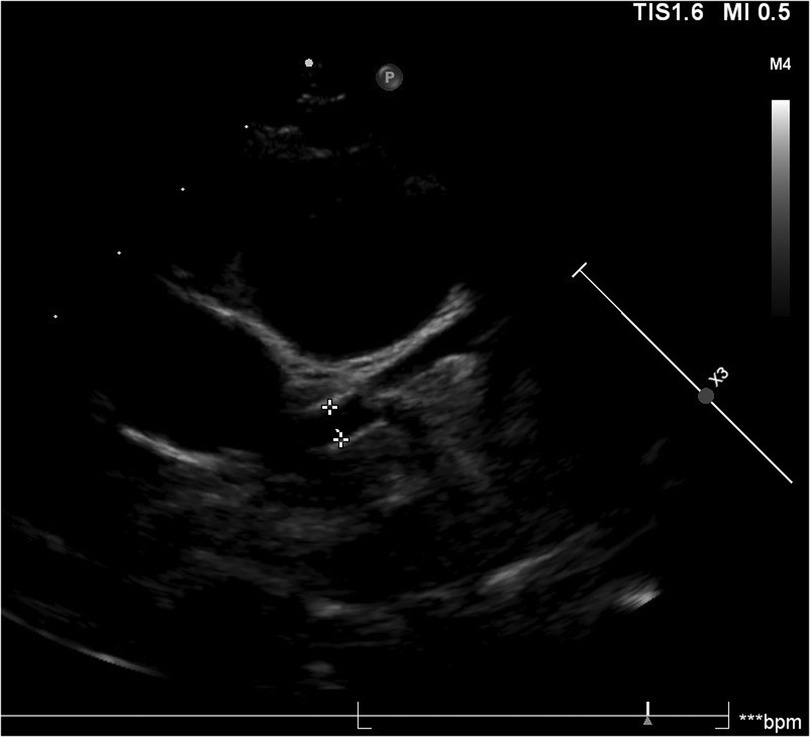

Among patients with fulminant myocarditis, one patient had concomitant Kawasaki disease (KD), which is particularly noteworthy. After the patient was diagnosed with fulminant myocarditis, IVIG and corticosteroid therapy were immediately administered. At 15 days after ECMO withdrawal, the patient developed a fever, a diffuse red miliary rash on the trunk, red and chapped lips, swelling of the hands and feet, and enlarged cervical lymph nodes. Echocardiography revealed the formation of small aneurysms in the left coronary artery (Figure 2). Therefore, the diagnosis of KD was confirmed according to diagnostic criteria. Myocarditis often occurs in patients with KD. A previous study revealed that the incidence of myocarditis in individuals with KD can reach 50% (32). Generally, myocarditis in KD patients is self-limiting or well managed with IVIG. This type of myocarditis is mostly mild and is accompanied by subclinical left ventricular dysfunction. However, in a small number of patients, left ventricular dysfunction can be observed, leading to congestive heart failure or cardiogenic shock (33). However, based on the patient's medical history and the course of the disease, the pathogenesis remains unclear.

Figure 2. Images of small aneurysms in patient with concomitant kawasaki disease. On the 20th day of the disease course, the patient presented with fever, generalized diffuse rash, red and chapped lips, bayberry tongue, bilateral cervical lymph node enlargement and swelling of hands and feet, and diagnosed with KD. On the second day after the diagnosis of KD, echocardiography revealed that the left coronary artery small aneurysms (Z = 2.53).